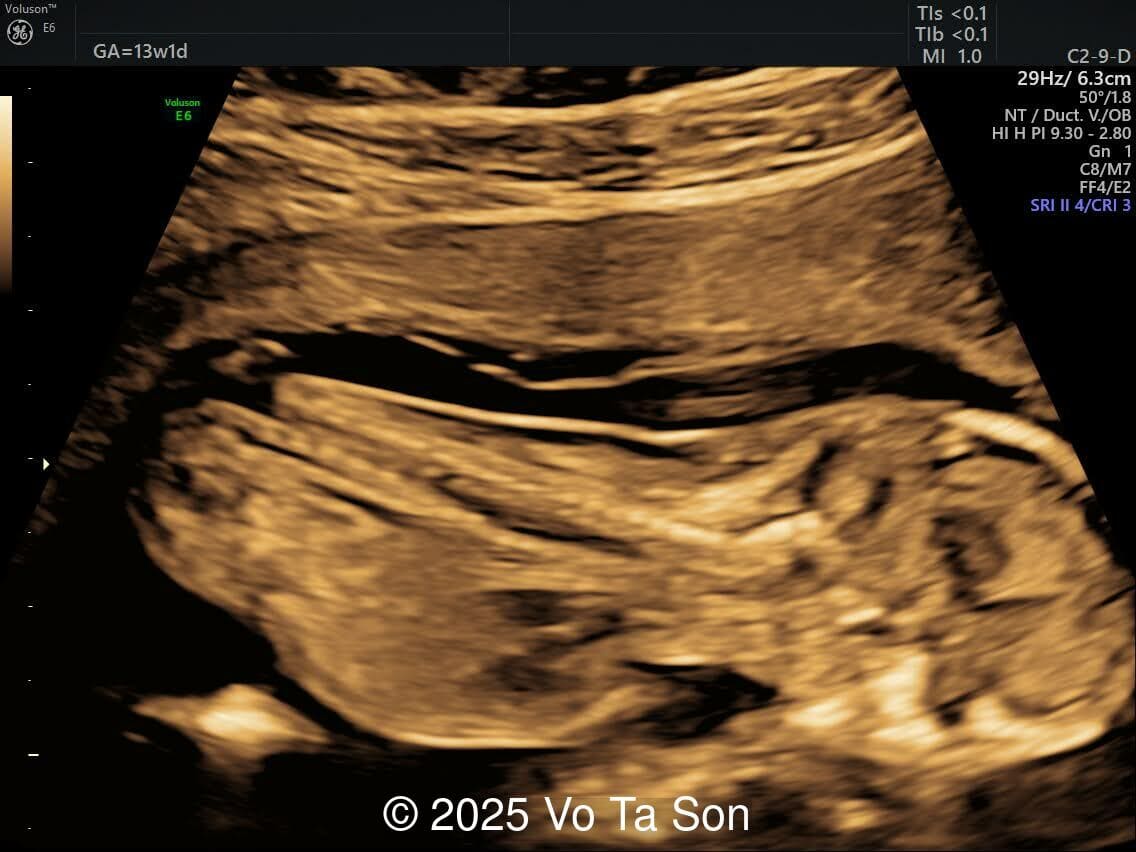

A 13-week pregnant woman underwent routine prenatal screening. The non-invasive prenatal test (NIPT) showed low risk for common aneuploidies (trisomy 21, 18, and 13). However, first-trimester anomaly scan revealed the following significant fetal abnormalities:

- Open spina bifida in the sacral region with dry brain and crash sign, BS/BSOB >1, direct lesion at sacral coccygeal spine

- Cystic-appearing placenta, suggestive of partial molar changes